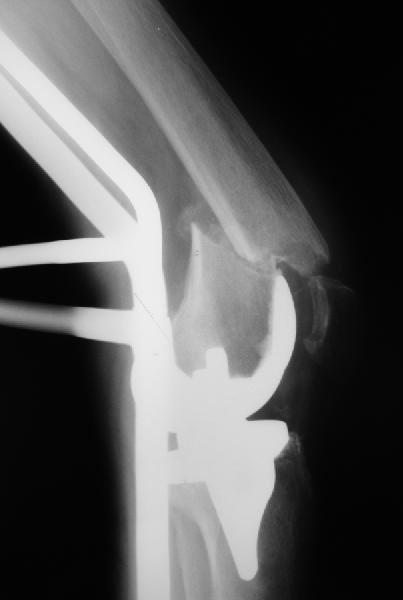

То, что планируется - наиболее распространенный подход. Еще менее инвазивный вариант - закрытый антеградный интрамедуллярный остесинтез. Мы используем гвозди, которые выпускаются предприятием ЦИТО, т.е. недорогие. Там в дистальное отверстие можно ввести 3 винта (2 снаружи и один навстречу), еще и угловая стабильность получается.

Уважаемый, Игорь! То что демонсрирует Александр Николаевич, высший пилотаж "neilinga" В нашей стране выполяется единичными спциалистами. Поэтому если не владеете методикой лучше пригласить к себе Челнокова. в случае накостного остеосинтеза, за который говорит ожирение и сопутствующая патология, не используте пластину Рыбинска. она не правильно предмоделирована и невесть из какого металла выполнена.поэтому неизвестно когда сломается при осевой нагрузке, и, кроме того,вы заведомо создадите вальгусную дефомацию, что повлечет за собой расшатывание компонентов. оптимальна в данном случае пластина "Synthes" скоминированными отверстиями. точно титан, идеально предмоделироана, винты надежно блокируются в отверстиях в отличие от Рыбинска.оперировать необходимо на спицевом дистракторе, спицы проводить перпендикулярно оси отломков. после репозиции под онтролем ЭОП чере два доступа пластину максимальной длины.дистальн заблокировать не менее 6 отверстий, проксимально-5.если нет возможности выполнить предложнные варианты, лучше пациентку перевести в отделение высшего уровня.Слишком высоки ставки. С уважением, Сергей.